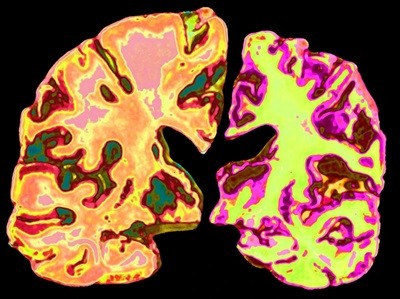

The work being funded in China is diverse. Keqiang Ye, a neurochemist at Shenzhen University of Advanced Technology, and his team are working on a drug called BrAD-R13, which is designed to mimic a protein called brain-derived neurotrophic factor (BDNF) that enables neurons to connect and communicate with each other. People with Alzheimer’s disease have low levels of BDNF in their brains. BrAD-R13 activates a receptor called TrkB, a natural target of BDNF5. This in turn protects neurons, possibly by reducing the formation of the amyloid plaques and tau neurofibrillary tangles that are hallmarks of Alzheimer’s disease.